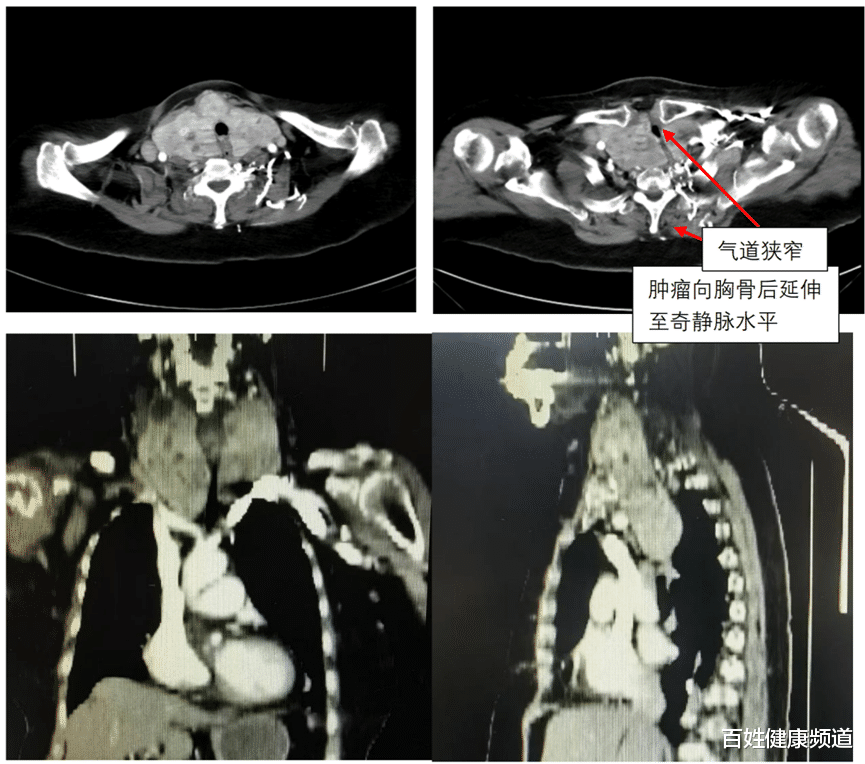

当天上午的义诊刚结束,来自中山大学肿瘤防治中心的李伟主任、李秋梨副主任医师就注意到了这位特殊的老人。一检查,两位专家瞬间绷紧了神经。老人的肿瘤不只是长在脖子上,而是已经“钻”进了胸腔深处,一直长到靠近心脏的大血管附近,将气道挤压得仅余一道细缝。

图源:中山大学附属肿瘤医院甘肃医院